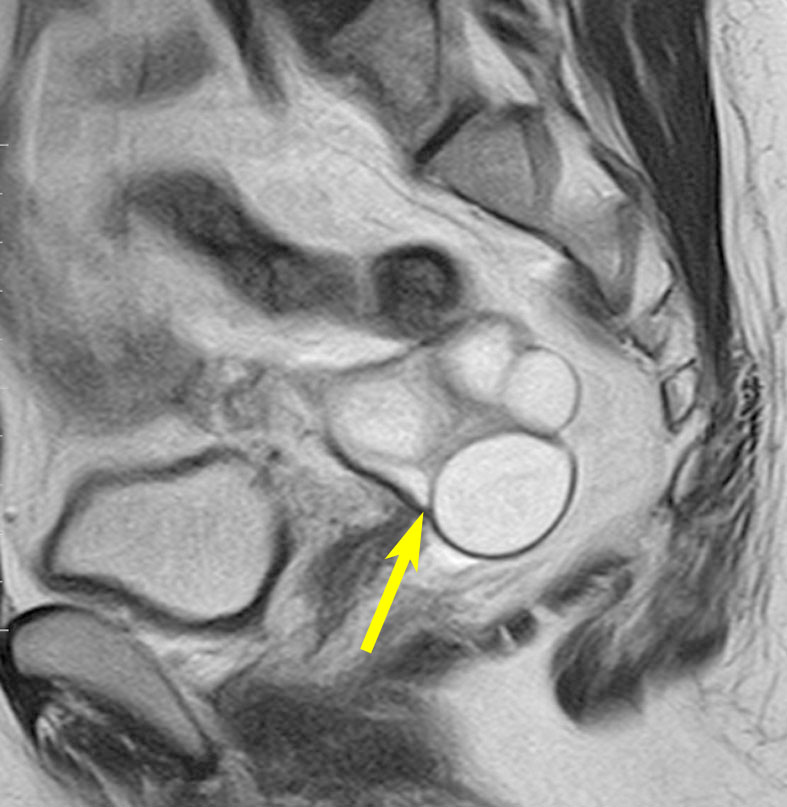

左は下垂体腺腫(緑の腫瘍)が内頚動脈に挟まれていることを示しています。

中央は手術前の下垂体腺腫で,視神経も正常下垂体も位置はわかりません。

右は手術翌日の画像です。黄色の矢印の先が残した正常下垂体組織です。桃色の矢印の先に視神経(視交叉)がはっきり見えています。術後の一時的な尿崩症がありました。クモ膜が残っているので髄液漏は生じませんでした。でも正常下垂体組織(黄色矢印)も視交叉も腫瘍に圧迫されてペラペラになっていますから,いつもうまく行くとは限りません。